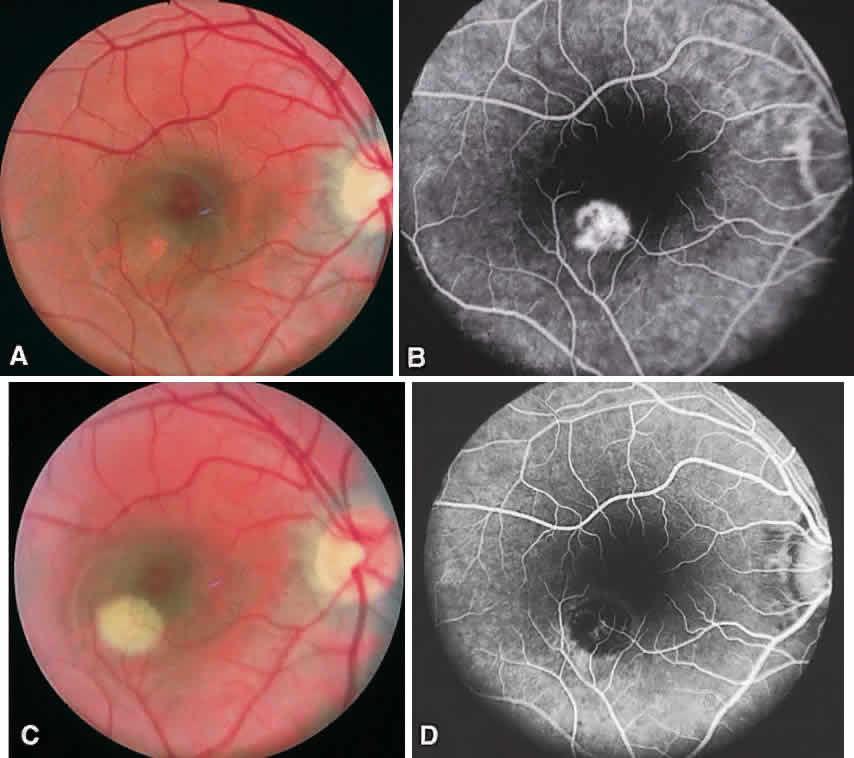

CSME was defined as retinal thickening within 500 μm of the center of the macula, intraretinal hard exudate within 500 μm of the center of the macula associated with adjacent retinal thickening, or retinal thickening greater than one disc area any part of which is within one disc diameter of the center of the macula (Fig. 3A). The beneficial effects of treatment demonstrated in this trial suggest that all eyes with CSME should be considered for focal photocoagulation (see Fig. 3B). Visual acuity was not a factor in determining the presence or absence of CSME and some eyes in the treated group had20/20 visual acuity. Many retinal specialists, how-ever, defer treatment in asymptomatic patients with20/20 visual acuity except when hard exudate is encroaching on the fovea.

When CSME is present, fluorescein angiography is helpful in ruling out macular ischemia as a cause for decreased vision. If significant perifoveal capillary nonperfusion is present, then macular photocoagulation is associated with a higher risk of producing an immediate and permanent reduction in visual acuity. If photocoagulation is performed in such cases, care should be taken to avoid directly treating the few remaining perifoveal capillaries.